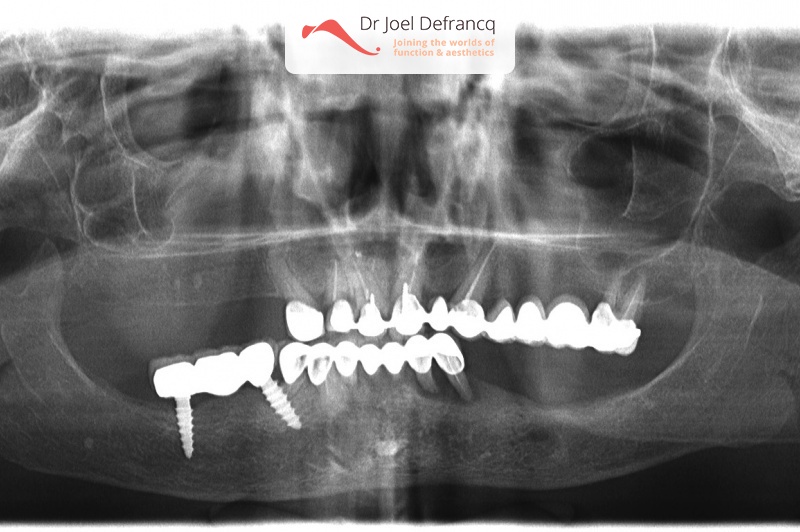

Bashira: all in for concept with immediate loading.

Dentale diagnose

- Klasse I

Behandeling tandheelkundige implantaten

- Vaste tanden op implantaten (bovenkaak)

- Vaste tanden op implantaten (onderkaak)